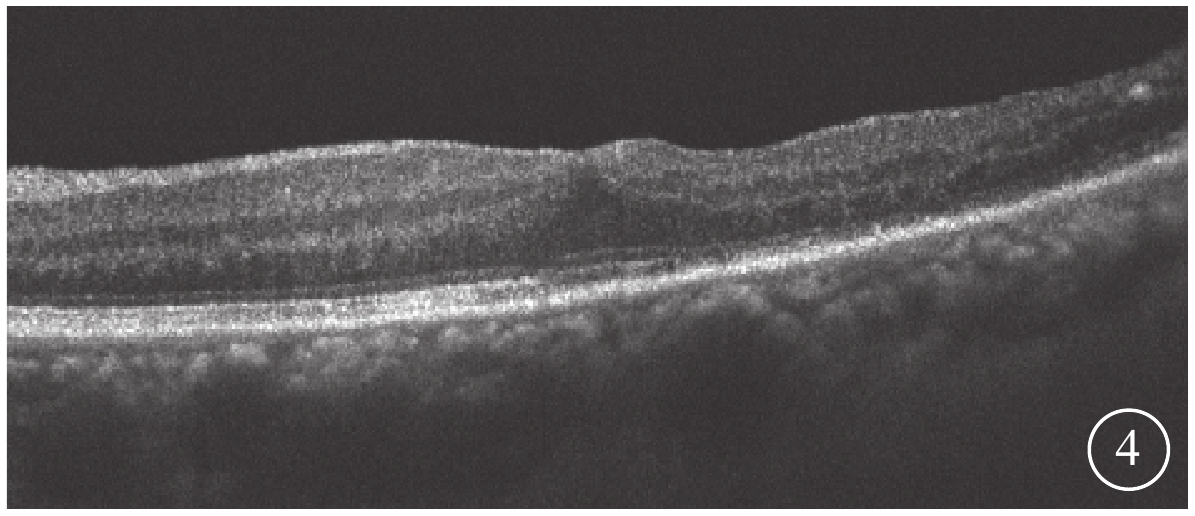

末次隨訪時,患眼BCVA為0.15~0.6,平均BCVA為0.42±0.24。患眼后房型人工晶狀體位正,黃斑部出血吸收。FFA檢查發現,患眼顳下視網膜動脈分支處強熒光點消失(圖3)。OCT檢查發現,患眼黃斑結構逐漸恢復(圖4)。所有患眼均未發生視網膜脫離、黃斑裂孔等并發癥。

圖4

圖1同眼手術后OCT像。黃斑中心凹形態恢復

圖4

圖1同眼手術后OCT像。黃斑中心凹形態恢復

末次隨訪時,患眼BCVA為0.15~0.6,平均BCVA為0.42±0.24。患眼后房型人工晶狀體位正,黃斑部出血吸收。FFA檢查發現,患眼顳下視網膜動脈分支處強熒光點消失(圖3)。OCT檢查發現,患眼黃斑結構逐漸恢復(圖4)。所有患眼均未發生視網膜脫離、黃斑裂孔等并發癥。

圖4

圖1同眼手術后OCT像。黃斑中心凹形態恢復

圖4

圖1同眼手術后OCT像。黃斑中心凹形態恢復